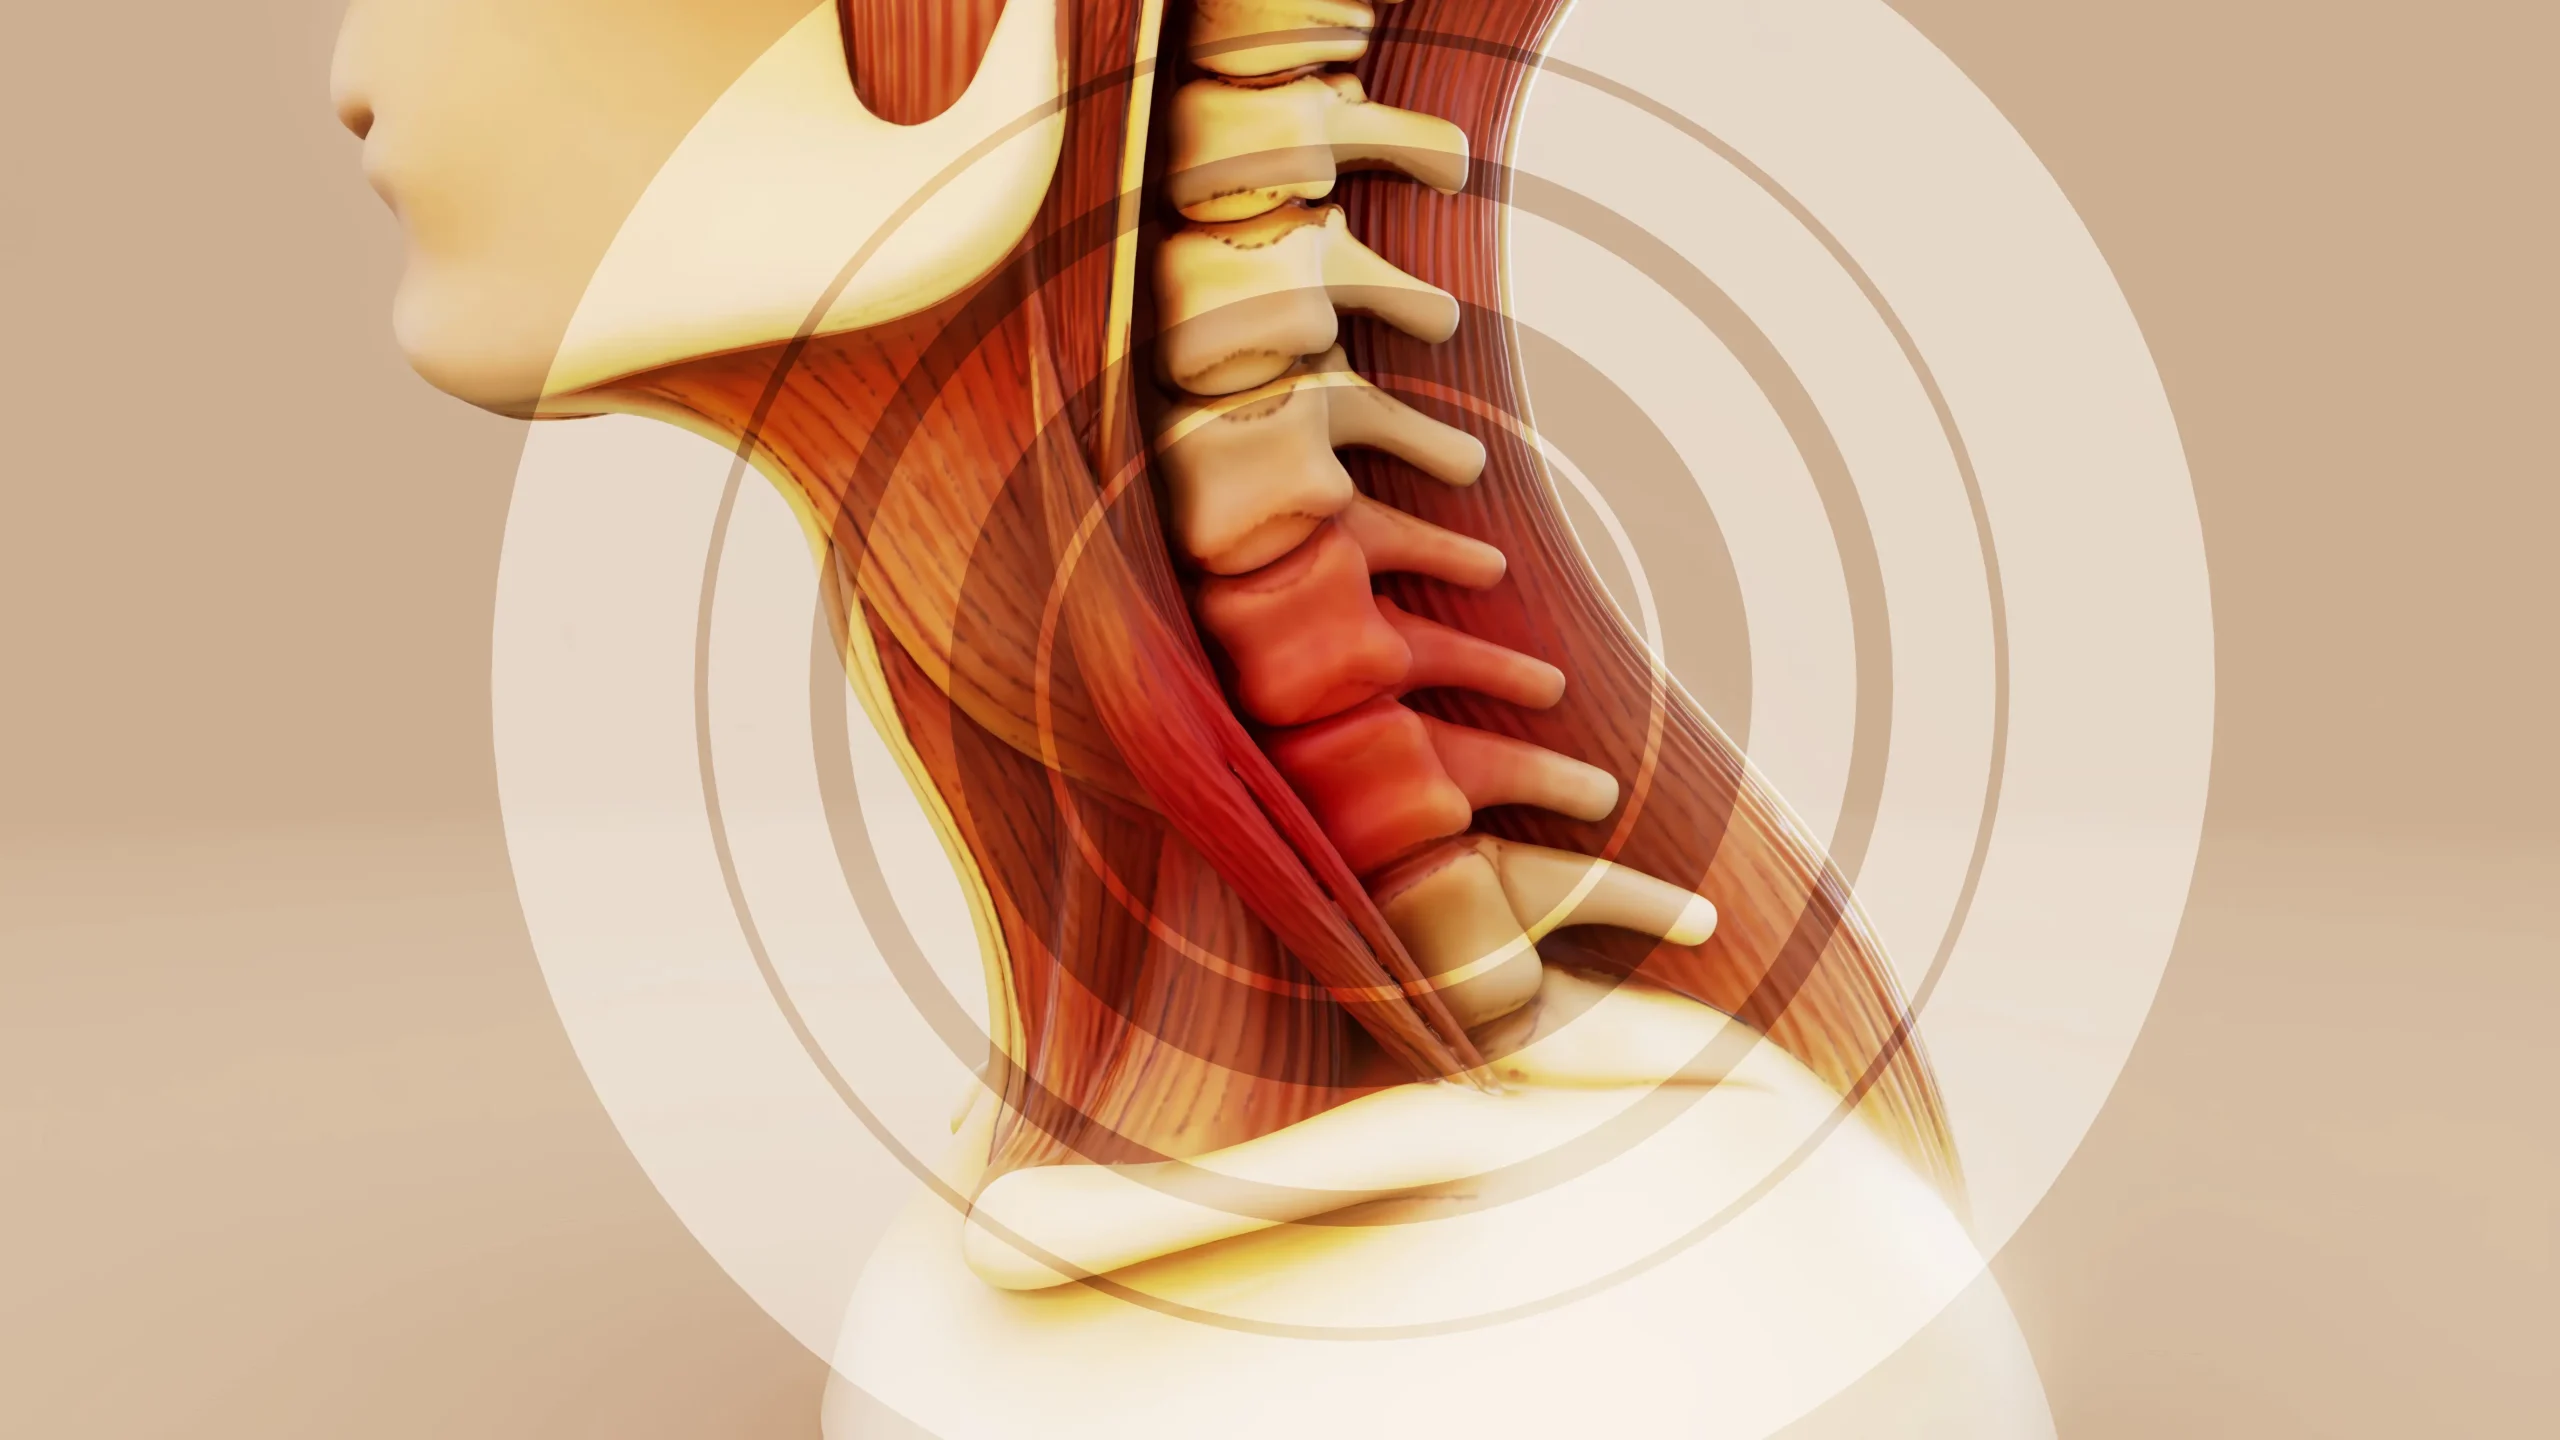

Telefon Kullanımı Boyun Sağlığını Nasıl Etkiler?

Boyun Fıtığı Masajı Nedir ve Faydaları Nelerdir?

Telefon Kullanımı Boyun Sağlığını Nasıl Etkiler?

Boyun Fıtığı Masajı Nedir ve Faydaları Nelerdir?